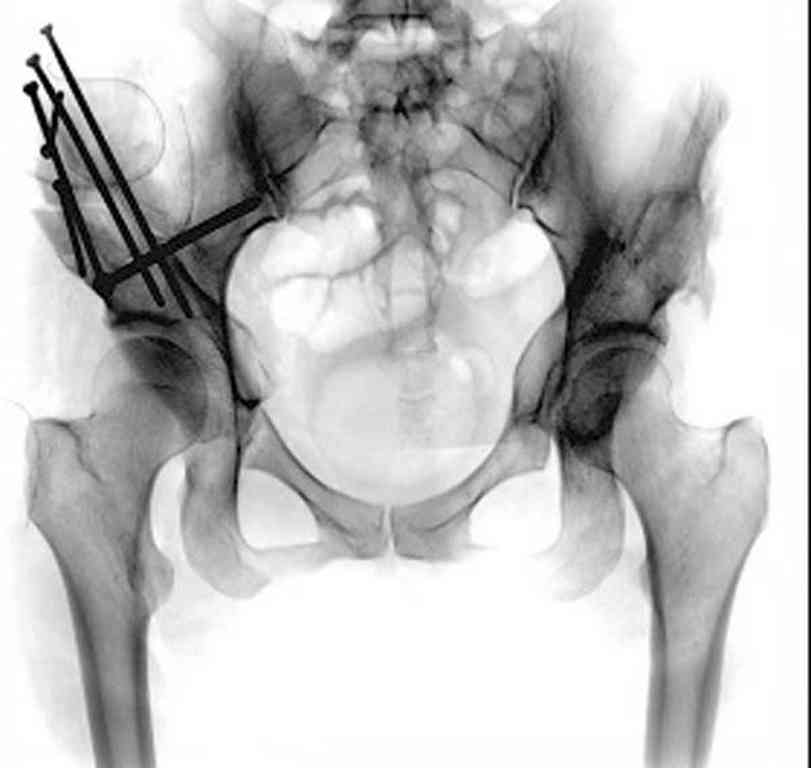

Представляю Р-снимки: обзорная, с отведением и с приведением.

Глубокоуважаемый Абдурашид. Здесь нет снимка с отведением. Если Вы сами сходили в рентгенкабинет и лично отвели пораженную конечность максимально возможно, а также дали максимально возможную внутреннюю ротацию-это одно!!!! Значит у пациентки тяжелейшая приводящая контрактура тазобедренного сустава!! И необходимо разобраться-миогенная или артрогенная? Если же Вы просто назначили указанный снимок и доверили произвести укладку рентгентехнику-это другое!!! Одному богу известно, что она делала, ведь на р-снимке отведения нет!

Все предыдущие корреспонденты предлагают вам достаточно простую вещь-смоделировать предлагаемую Вами операцию (т.е. дать отведение и внутреннюю ротацию) и посмотреть, как изменятся соотношения в суставе. Не обижайтесь, но судя по представлению клинического случая угловые величины, характеризующие пространственные соотношения в тазобедренном суставе, ваши рентгенологи не считают.

Уважаемый Игорь Владимирович. диссертации М М Камоска, и В Е Баскова я нашел, но почему-то не могу открывать, и еще в данном случае имеется дисплазия т/б за счет недоразвития крыши в/впадины да и всей подвздошной кости, маргинального вывиха или латеропозиции головки вследствие лечебных ощибок нет, головка стоит на месте. Р-граммы сделал сам, но почему-то у больной отведение и внутренная ротация стали очень болезненной, и сухожилия приводящих мышц сильно натягивается.(контрактура артро-миогенная).

Глубокоуважаемый Игорь Владимирович! Признаюсь допустил ошибку, из-за напряженности работы и нехватки времени, когда повторно внимательно посмотрел все понял и не успел исправить ошибку до Вашего поста, конечно скошенность крыши в пределах 40гр,часть головки кнаружи линии Омбредана-Перкинса , облитерация дна вертлужной впадины и т.д.-это ДМВБ.